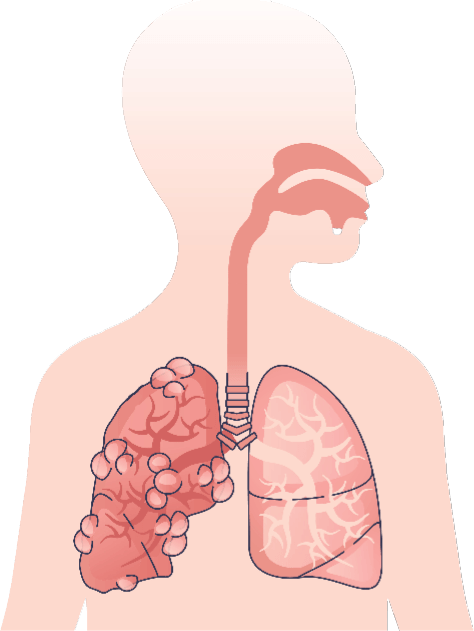

MECHANISM OF ACTIONS (MOA)

EA 575® is also unique to help improve respiratory function in patients with bronchitis.

- The EA 575® is an active ingredient from natural ivy leaf which liquefies the sticky mucus trapped in the air passages of the lungs.

- It then acts as an expectorant, allowing the mucus to be coughed up more easily.

- As the air passages relax and widen, you are able to breathe better and more comfortably.